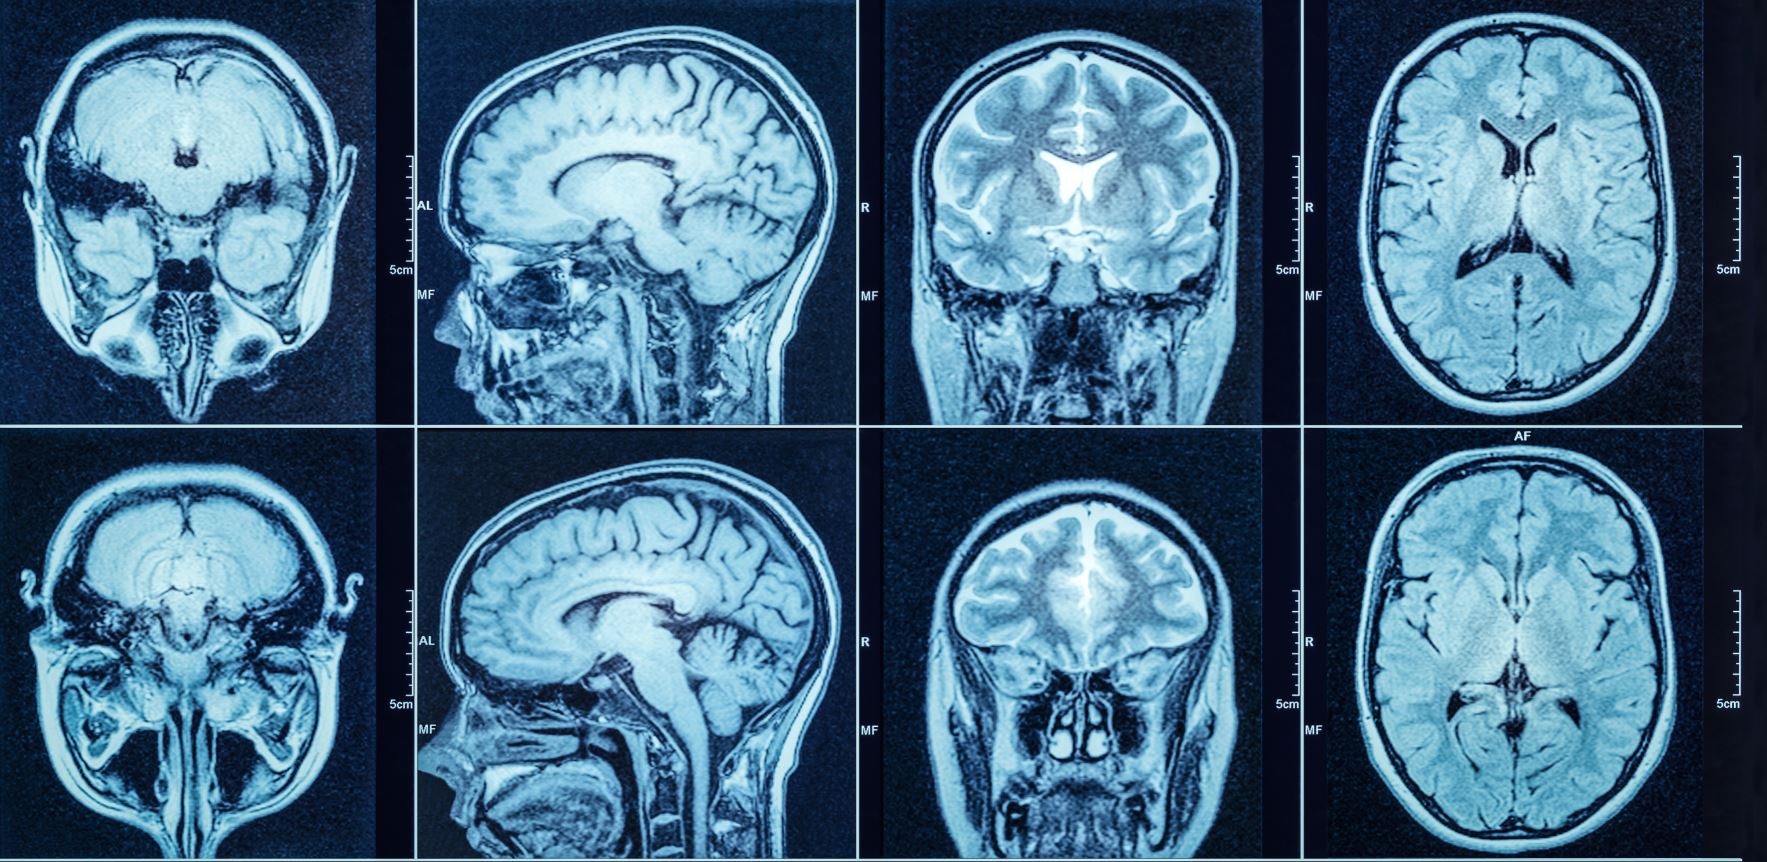

180 newborn babies were recruited and underwent brain MRI scans.

They suggested that a history of paternal stress in childhood or adolescence is associated with alterations in the development of the white matter of children's brain regions in early childhood (particularly the corpus callosum, right superior corona radiata and retrolenticular parts of the internal capsule).